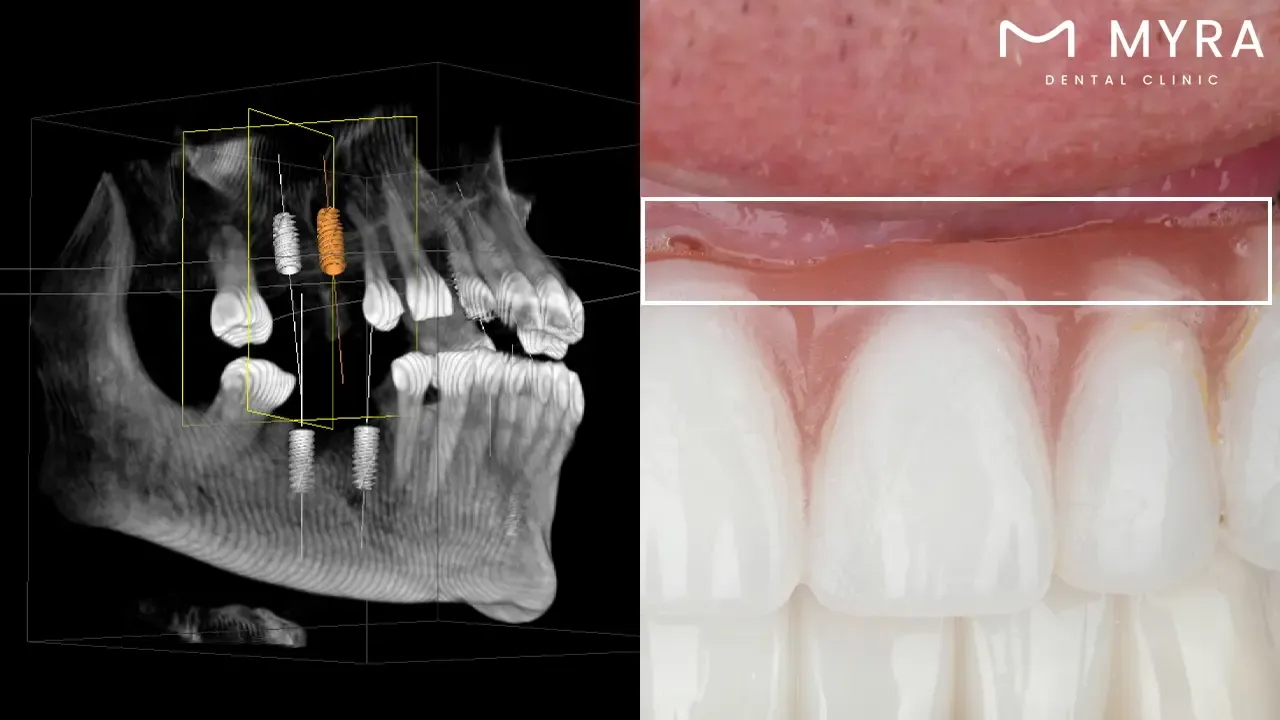

An implant overdenture or an implant-supported overdenture is a type of removable dental prosthesis that is safely attached to dental implants that are placed in the jawbone. The type of denture blends the benefits of traditional dentures with the stability and support of dental implants.

Traditional detachable dentures are held in place by suction, adhesives, or the shape of the mouth. An implant overdenture is made to snap onto dental implants and be supported by them. Dental implants are small titanium posts that are carefully put into the jawbone to act as new tooth roots. The implants fuse with the bone over time, giving the overdenture a stable base through a process called osseointegration.

The upper and lower jaws use an implant overdenture. The upper and lower jaw implant overdenture is made as a full overdenture that replaces all the teeth in an arch, or as a partial overdenture that replaces only some lost teeth. The overdenture is attached to the dental implants with ball attachments, bar attachments, or locator attachments. These allow the denture to stay in place securely while being easy to take out for cleaning and upkeep.

Implant overdentures have several benefits over traditional removable dentures, such as better stability, better chewing ability, less irritation to the oral tissues, and better retention. The answer to the query ‘What are implant overdentures?’ is that implant overdentures give people who are missing teeth more confidence and comfort because they make it less likely that their dentures slip or move around. Implant overdentures make a big difference in the quality of life for people who want a more stable and useful way to replace missing teeth.